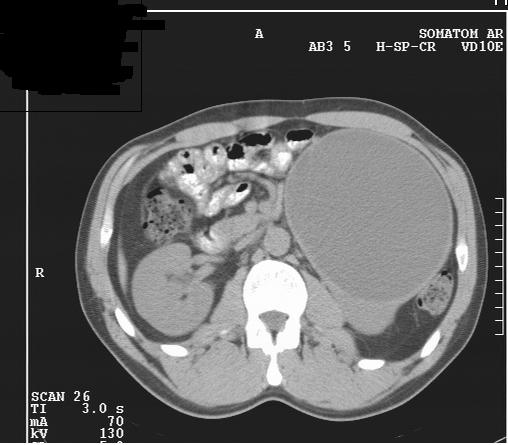

М. 37 лет, жалоб нет, амб. приём, причина назначения УЗИ ОБП: СОЭ 42мм

б\б и м\э консист., как говорится.   Исходит из н\ полюса левой почки

Вложения

2.JPG

3.JPG

4.JPG

КТ сделали без контрастирования, смысл такого КТ??? Диагностической ценности-ноль.